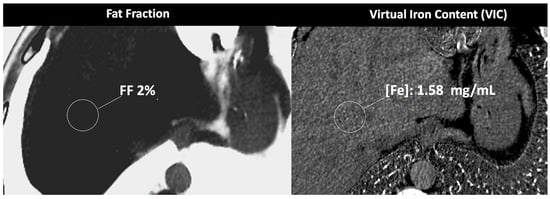

Figure 9.

DECT-based assessment of fat and iron deposits. CT images demonstrate a fat fraction of 2% and a virtual iron concentration of 1.58 mg/mL, which rules out fatty infiltration or iron overload in this patient.